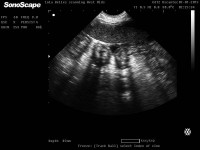

THE APPEARANCE OF A 'WATER PUP' ON A CANINE ULTRASOUND SCAN

The Vet Image Solutions Facebook group is a fantastic learning resource for those looking to learn more about canine reproduction and scanning. Recently, Jennie from Lincoln Canine Scanning shared this scan with the following comment:

English Bulldog 43 days?? Water pup here, could see it better on the screen but moved just as took the picture - abdominal wall seen with fluid around anterior abdominal wall.